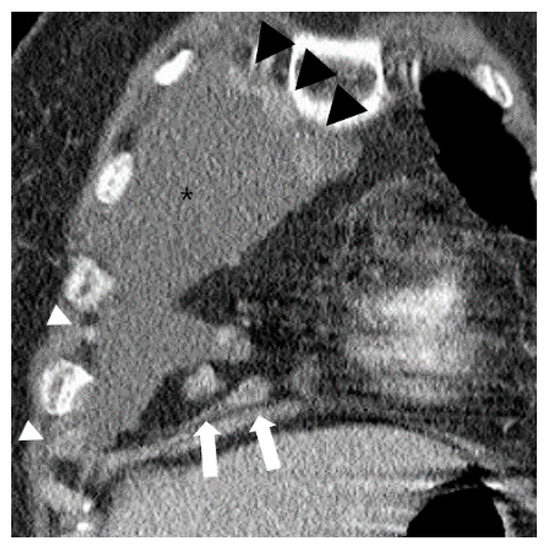

Figure 3.

A case of typical malignant pleural effusion (asterisk) in a 73-year-old female on chest CT. Over 1 cm enlarged lymph nodes are noted in ipsilateral paracardiac fat (white arrows). Multiple contrast enhanced pleural nodular thickenings are also noted (white and black arrowheads).

Multiple nodular areas of pleural thickening with contrast enhancement (black and white arrowheads) are noted in the right pleural effusion (asterisks) on a coronal CT image at the level of the right ventricle. Note multiple enlarged lymph nodes measuring >1 cm (white arrows), but absence of phlegmonous appearance in the ipsilateral paracardiac fat.